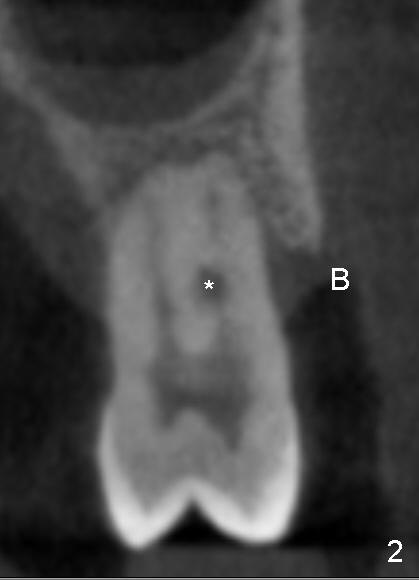

After local anesthesia and rubber dam isolation, caries is removed from the distal cervical region. Access is provided occlusally. Initial debridement is done with hand files until #20 with copious irrigation with 3% sodium hypochlorite. The shortcoming is bleach leakage. While #15 and 20 files are inserted in the buccal and lingual canals, the distal cavity is filled with Cavit temporarily. There is no more leakage, while the canals remain patent. RCT is finished with ease (Fig.4). Then the distal cervical Cavit is removed, followed by routine composite build up (Fig.5 C). The patient remains asymptomatic for 2 months now.